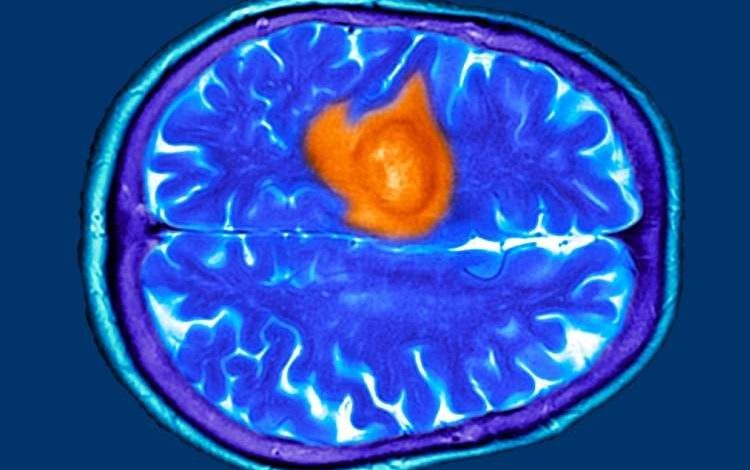

هفت نشانه پنهان تومور مغزی که ممکن است آنها را عادی بپندارید

به گزارش نیوزلن و به نقل از ساینسآلرت، پژوهشهای اخیر نشان میدهد که بیماران و پزشکان عمومی در مراحل اولیه اغلب این نشانهها را نادیده میگیرند و همین امر باعث تأخیر در تشخیص میشود. از آنجا که درمان تومور مغزی در مراحل پیشرفته دشوارتر است، شناسایی علائم اولیه اهمیت ویژهای دارد.

تومور مغزی میتواند با علائمی مشابه بیماریهای رایج مانند اضطراب، عفونت سینوس یا یائسگی بروز کند. در پژوهشی که بر پایه مصاحبه با بیماران انجام شد، هفت علامت اصلی شایع اما فریبنده شناسایی شد. نخستین مورد، دشواری در یافتن کلمات است؛ برخی بیماران در صحبت کردن یا کامل کردن جمله دچار وقفه میشدند، موضوعی که ابتدا به استرس یا خستگی نسبت داده شد. دوم، مهذهنی یا Brain Fog است که با ناتوانی در تمرکز و فراموشی همراه میشود. اگر این حالت با مشکلات گفتاری یا بینایی همراه شود، نیاز به بررسی پزشکی دارد.